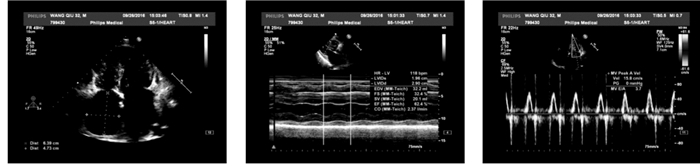

男,32岁,因间断胸闷、气短3年,加重2周入院。3年来患者因胸闷、气短多次就诊于外院,诊断为限制型心肌病。近2周上述症状加重,偶有端坐位呼吸及夜间阵发性呼吸困难,伴腹胀、食欲减退及少尿。既往吸烟史约20年,平均3-4支/d,已戒烟。否认高血压、糖尿病史、相关家族遗传病病史及寄生虫感染病史。入院查体:血压120/80 mmHg,端坐位,口唇发绀,颈静脉怒张,颈静脉搏动明显。双肺呼吸音粗,双下肺可闻及少量湿啰音。心界扩大,心率108次/min,律不齐,可闻及舒张晚期奔马律。肝肋下5 cm,双下肢中度凹陷性水肿。胸部CT示双心房增大,双肺散在炎症,双侧少量胸腔积液。心电图示(图 1)心房扑动,2:1-4:1传导,V1-V5导联T波倒置。肝、肾功能,血糖、心肌酶学、甲功八项未见异常。NT-pro BNP:6 110 pg/ mL(正常 < 100 pg/mL)。经胸心脏彩超示(图 2):左房(57.1 mm ×46 mm ×65.0 mm)、右房(47.3 mm×63.9 mm)增大;右室大小17.7 mm、左室大小32.7 mm;右室前壁厚度8 mm、室间隔17.7 mm、左室后壁13.3 mm;EF 62.4%;静息状态下左室壁收缩运动协调、运动幅度正常、心尖部收缩期近闭塞、左室流出道流速不快,E/A= 3.7,心内膜无明显增厚及回声增强,三尖瓣中度返流,二尖瓣轻度返流,心包少量积液。入院诊断为非梗阻性肥厚型心肌病舒张性心衰心律失常-心房扑动心功能Ⅳ级。经积极减轻心脏负荷、抗心律失常、抗感染、抗凝等对症治疗20 d,患者无明显呼吸困难,可平卧,双下肢无水肿。心脏MRI(图 3)结果示:双房增大,左、右心室壁及室间隔明显增厚、心室收缩功能正常,舒张功能受限;心脏灌注分析示心肌、心内膜未见延迟强化,支持上述诊断。出院后继续给予β受体阻滞剂、钙通道阻滞剂、抗凝及利尿治疗,随访中。

| 心电图示:心房扑动,2:1-4:1传导 图 1 患者心电图 |